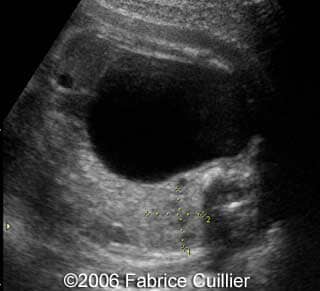

This is a 24- year-old-primigravida scanned at our unit at 21 weeks. During the first trimester, the nuchal translucency and the triple test were normal. At the end of the second trimester, the sonographer diagnosed a left polycystic kidney. The right kidney was normal with a normal corticomedular differentiation. The bladder was also normal. The patient refused additional investigations. We performed a scan at 21 weeks. The ultrasound findings were:

• an abnormal polycystic left kidney (34 X 17 mm) with an abnormal corticomedullar differentiation. This kidney was on the lumbar fossa.

Transverse view of the normal right kidney and the abnormal left kidney